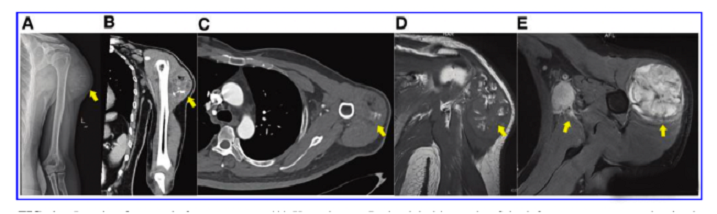

接受iPS細(xì)胞治療患者的畸胎瘤。(A) 在左上臂的三角肌中,觀察到一個(gè)圓形的混合密度腫塊,邊界不清,為9.6±5.2cm。(B) CT冠狀掃描顯示三角肌內(nèi)有一圓形混合密度腫塊,邊界不清。(C)增強(qiáng)CT軸向掃描顯示不均勻和中度強(qiáng)化。(D)MRI T1W以等信號(hào)為主,有不規(guī)則的高低信號(hào)區(qū)。(E) T2W也顯示高信號(hào)和斑片狀低信號(hào)區(qū),左腋窩有多個(gè)淋巴結(jié)腫大。

文中展示了該未成熟畸胎瘤的臨床,放射學(xué)和病理學(xué)特征,作者認(rèn)為這種腫瘤不同于典型的未成熟畸胎瘤,特點(diǎn)是快速增長(zhǎng)和局部淋巴結(jié)轉(zhuǎn)移,該新生腫瘤對(duì)典型化療方案沒(méi)有反應(yīng),磁共振成像顯示腫瘤的不均勻強(qiáng)化和豐富的血供。